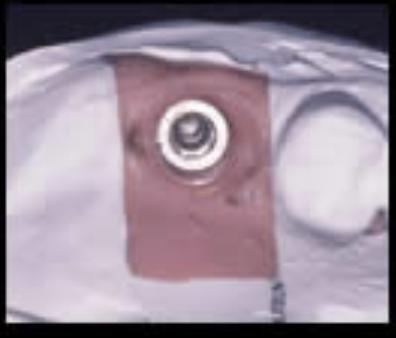

人工歯根と接合するアバットメントを示します。

治療過程

抜歯後、歯周病処置、歯内療法処置、咬合高径改善、プロビジュナルレストレーションを経て最終補綴をおこないました。